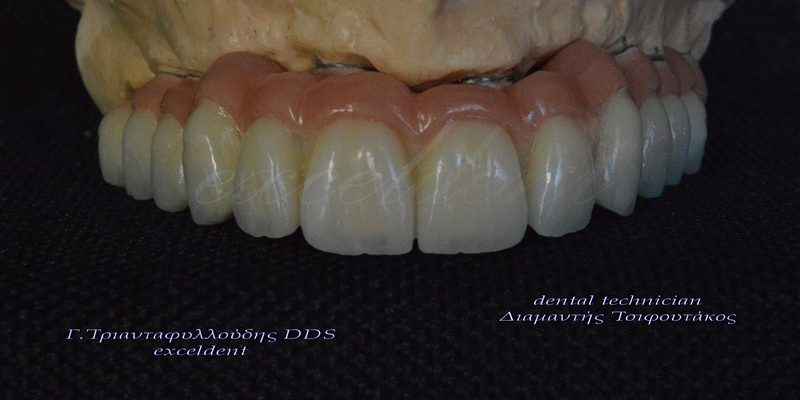

Ολική αποκατάσταση στόματος με ακίνητες γέφυρες στηριζόμενες σε εμφυτεύματα

Ακόμη ένα περιστατικό ολικής στοματικής αποκατάστασης ασθενούς με ακίνητες γέφυρες στηριζόμενες σε εμφυτεύματα(8 στην άνω και 7 στην κάτω γνάθο).